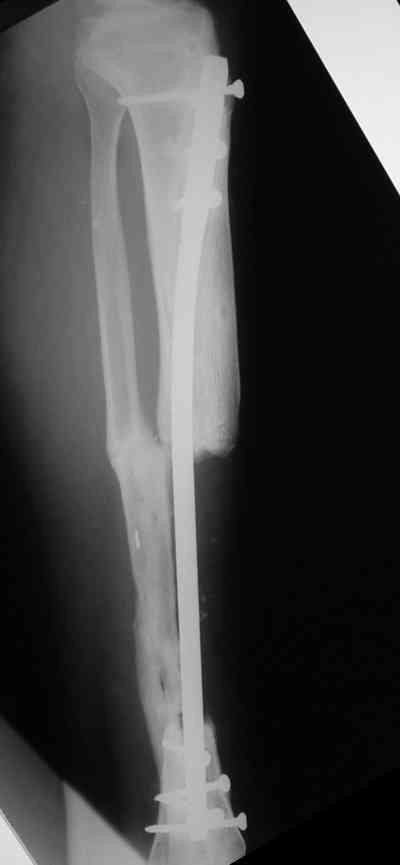

Владимир, свободная костная пластика на фоне свища вряд ли оправдана. Почему не рассматриваете вариант транспорта кости по Илизарову? Что собираетесь делать с латентной инфекцией? Одни антибиотики не помогут, необходима полноценная хирургическая обработка, Мы бы подумали о цементном спейсере с антибиотиками, бусах. После купирования инфекции переходить к замещению

дефекта: за счет удлинения концов б\б кости или тибиализации м\б. На начальном этапе фиксация только в аппарате, в последствие для удержания достигнутого можно перейти на фиксацию интрамедуллярным штифтом (см. вложенные файлы)